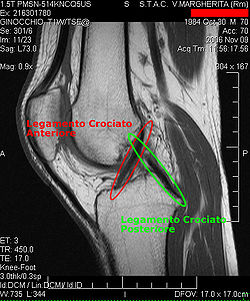

Procédés d'imagerie

Le diagnostic peut être confirmé par imagerie (IRM). Mais il faut noter que l'interprétation de l'IRM seule pour le diagnostic de rupture de LC conduit à 20 % de faux diagnostics. Cela dépend des images de coupe et de la position appropriée du genou pendant l'IRM. Le radiologue doit connaître avec précision les circonstances qui ont conduit à la blessure, et avoir aussi une bonne expérience de l'étude d'une articulation blessée, pour éviter les faux diagnostics. Pour comparer avec l'IRM, le taux d'erreur du test de Lachman, bien plus simple à accomplir, n'est que de 10 %[108],[109],[110],[111]. L'IRM est donc généralement moins sensible et moins spécifique que l'examen clinique par un orthopédiste qualifié[112]. Le résultat de l'IRM n'a que relativement rarement une influence sur la formulation finale du diagnostic[113] et ne devrait pas servir de remplacement pour une anamnèse soigneuse et la palpation[114]. Plusieurs études arrivent à la conclusion que l'IRM n'a de sens que pour des blessures complexes difficiles à expliquer, et là, pour éviter de poser un diagnostic négatif[115],[116],[117].